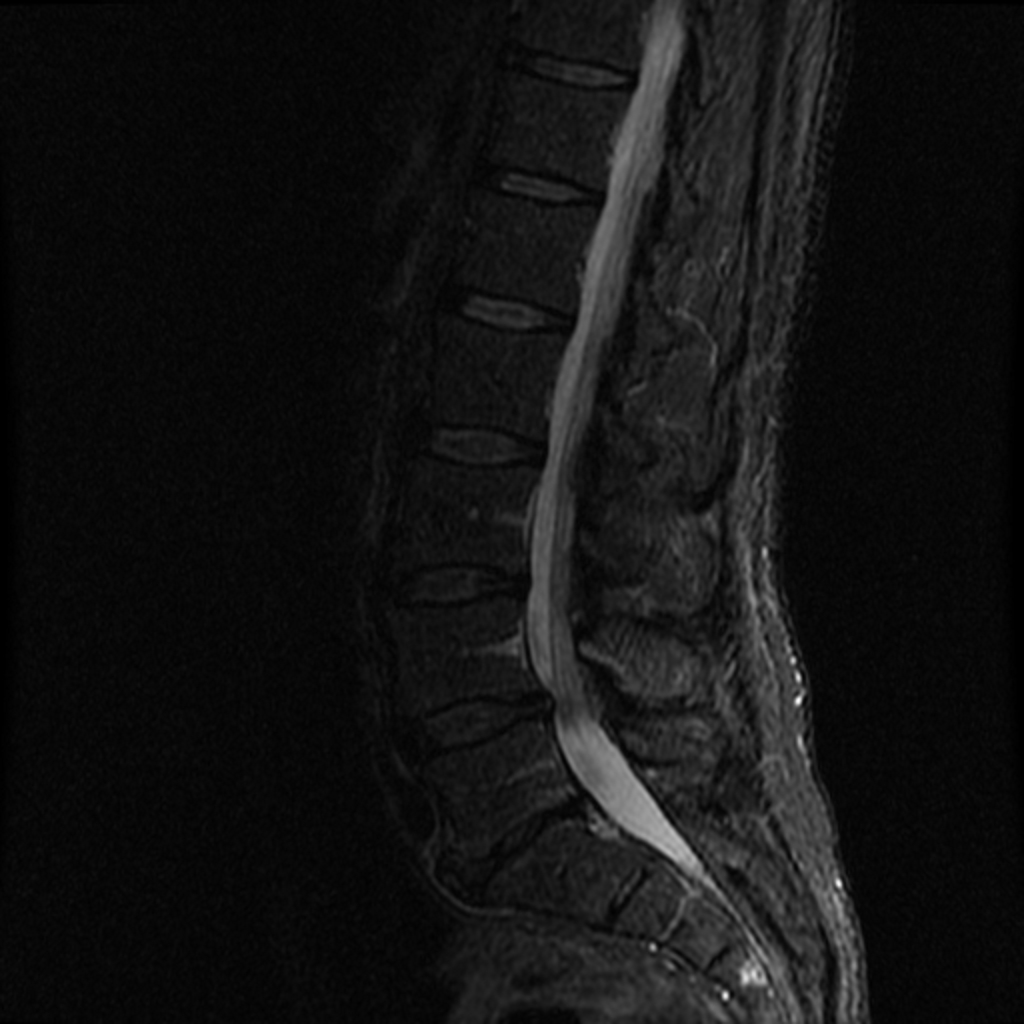

7. 1. 영상의학적 진단

허리뼈 질환은 X선, CT, MRI 등 영상의학적 검사를 통해 진단할 수 있다. MRI는 척추, 추간판, 신경 등 연부 조직의 상태를 자세히 확인할 수 있어 척추 질환 진단에 유용하게 사용된다.